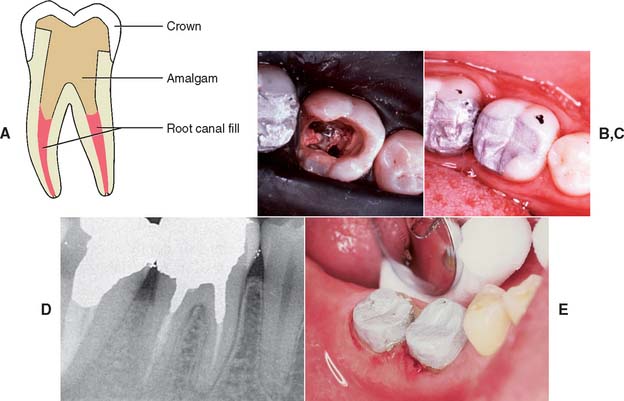

If the coronal structures are largely intact and loading is favorable, as on anterior teeth that are farther removed from the fulcrum (see Chapter 4), a simple filling can be placed in the access cavity (Fig. 12-2A). However, if a substantial amount of coronal structure is missing, a cast post and core is indicated instead (Fig. 12-2B). Molars are often restored with amalgam or a combination of one or more cemented posts and amalgam or composite resin (Fig. 12-2C and D).

Fig. 12-2 A, An anterior tooth with an intact clinical crown can be predictably restored with a composite restoration in the access cavity. B, When most coronal tissue is missing, a cast post and core is indicated to obtain optimal tooth preparation form. C, In mandibular molars, an amalgam foundation is retained by a cemented prefabricated post in the distal canal. D, In maxillary molars, the palatal canal is most often used.

Complete coverage is recommended on teeth with a high risk of fracture. This is especially true for maxillary premolars, which have been shown to have fairly high failure rates if restored with two or three surface amalgam restorations.18 Complete coverage gives the best protection against fracture, because the tooth is completely encircled by therestoration. However, when a metal-ceramic crown is to be used, considerable tooth reduction is required, which results in further weakening of the remaining tooth structure. In general, when significant coronal tooth loss has occurred, a cast post and core (Fig. 12-7) or an amalgam foundation restoration is needed.

Mandibular premolars and molars with a reasonable amount of remaining coronal tooth structure, when coupled with a circumferential cervical band of tooth structure with restricted taper of about 2 mm, can often be restored with amalgam directly condensed into the chamber. Core buildups in molars with one or more missing cusps benefit from one or more cemented posts around which the amalgam can be condensed. The posts provide the additional retention, which was compromised because of the missing tooth structure. In mandibular molars, the larger distal canal is recommended for post placement. In maxillary molars, the palatal canal is used (see Fig. 12-2C and D).